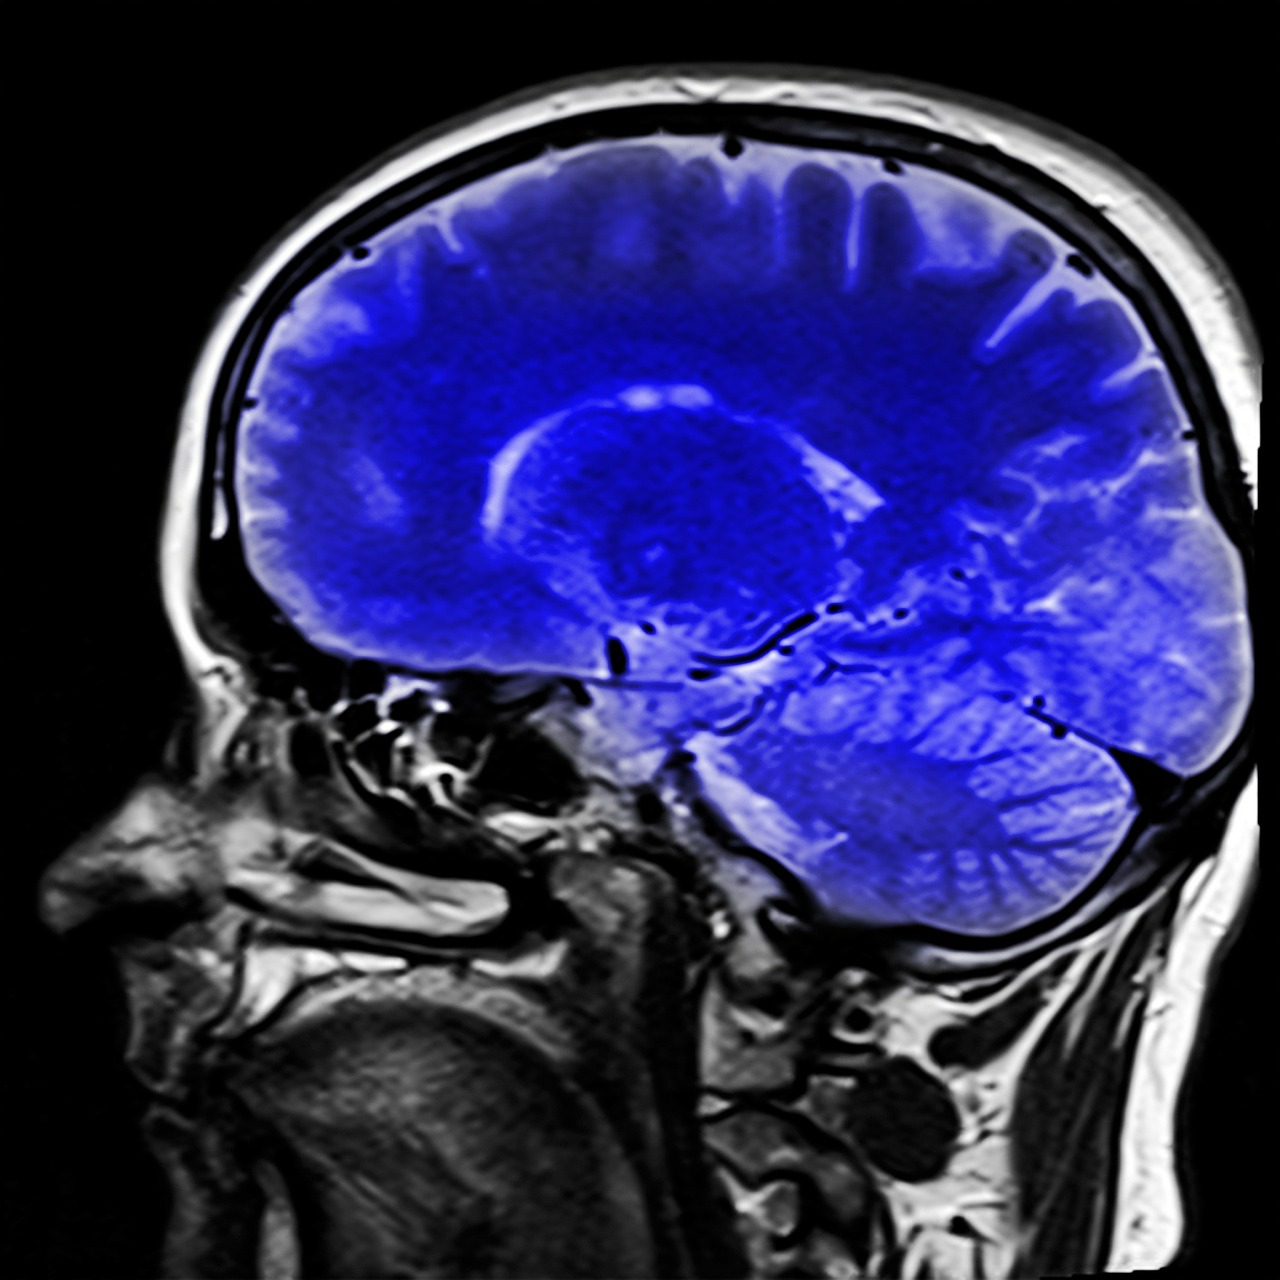

Ventromedial prefrontal cortex: signals safety. Brain_human_sagittal_section.svg: Patrick J. Lynch, medical illustrator, CC BY-SA

Patients with OCD could initially learn which face predicted threat. But once this had been reversed they were unable to differentiate between the new and the old threatening stimulus – they treated both as threatening. We think this is because they never really learned that one of the faces was truly safe – something which was reflected in their brain activity. Unlike in the healthy participants, there was no signal from the OCD patients’ ventromedial prefrontal cortex, a brain area that normally signals safety.